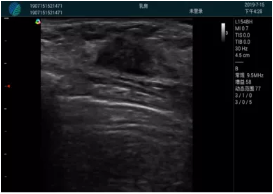

腺體內部清晰顯示一低回聲塊影,形態(tài)不規(guī)則,邊界模糊,邊緣呈毛刺狀,內部見砂礫樣鈣化

M20引導下穿刺活檢術

M20引導下平面內穿刺取出的腫塊組織